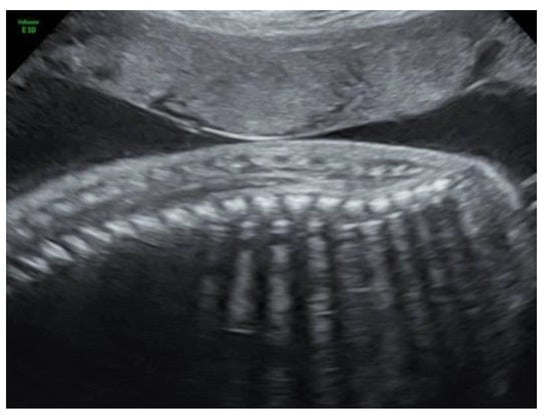

Figure 2). The lateral ventricles were not dilated. Ultrasound examination of the spine revealed a closed skin except for a minimal fistula in the sacro-coccygeal region (

Figure 3,

Figure 4 and

Figure 5). Furthermore, an abnormal gap between the second and third digit was seen on both hands as well as a syndactyly between the first and second toe. Cardiac sonography was normal at both 17- and 24-weeks GA, with a normal four-chamber view, outflow tracts, and three-vessel view. An amniocentesis was performed to rule out genetic anomalies and to measure alfa 1-fetoprotein. Additionally, a fetal MRI was carried out mainly to assess the fetal spine, as the cerebral findings all indicated the presence of an open neural tube defect. MRI analysis confirmed the hydroureteronephrosis as well as the lemon-shaped skull, Arnold–Chiari malformation 11mm below the foramen magnum, absent cerebrospinal fluid around the cerebellum, and possible mild tethering of the cord. However, MRI failed to demonstrate an open spina bifida or any skin defects. The Alfa 1-fetoprotein was elevated, further reinforcing the assumption of a classic spina bifida. QF-PCR showed no aneuploidy for chromosomes 13, 18, 21, X, or Y, but SNP array demonstrated a terminal multiplication of approximately 56 Mb of the long arm (3q23qter) of chromosome 3: arr 3q23q29(141903905-197845233)x2~4. The nature of the multiplication could not be deduced. Interphase FISH with probes in chromosomal regions 3q26 and 3q27 showed 4 copies of both chromosomal bands in approximately 50% of the interphases. Metaphase FISH proved that the 2 extra copies were located on a marker chromosome. Chromosomal examination of the parents showed no anomalies, demonstrating that the aberration occurred de novo in the fetus. Note, a genome-wide NIPT analysis on a blood sample taken at 27 weeks GA failed to detect this anomaly despite its size, indicating this to be a true fetal mosaicism of type 5 (TFM5).

9]. The diagnoses can be made in subtle cases, such as this one, by identifying a lower position of the conus medullaris. On the other hand, it is a difficult examination that is not suitable for routine screening but can help if suspicion is raised. Dorsal dermal sinuses are even more difficult to diagnose, as there is no presence of a cyst or mass. In these cases, the nerves and spinal cord are not usually affected and, therefore, in contrast to open lesions, this disease has a minimal functional impact. To our knowledge, this is the first case of closed spina bifida with a dorsal dermal sinus that is accompanied by secondary cranial abnormalities that has been diagnosed prenatally. In this fetus, a severe hindbrain herniation was detected while prenatal imaging demonstrated an intact spine and skin, both on MRI and ultrasound. Only by means of expert ultrasound, after increased suspicion of the diagnosis of spina bifida due to the elevated alfa 1-fetoprotein, could we find a small fistula between the skin and the spinal canal.